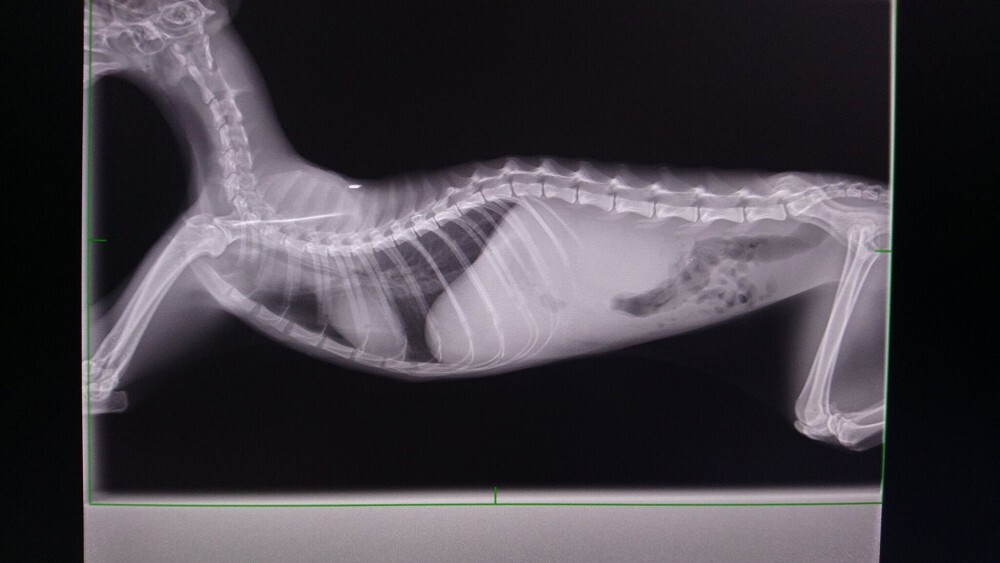

經醫師檢查發現瘦瘦有中度貧血.白血球極度偏高.黃疸.肝指數輕微偏高

也是愛滋感染的貓咪

超音波檢查發現腎腫大且大部分病灶都在腎臟皮質處.有少量腹水動物近況說明: 住院治療前醫師就有說貓咪狀況不樂觀

留院第三天醫師來電說瘦瘦出現神經症狀跟抽筋,建議讓瘦瘦安樂

醫師診斷是乾式腹膜炎,離開我們只是時間早晚問題。